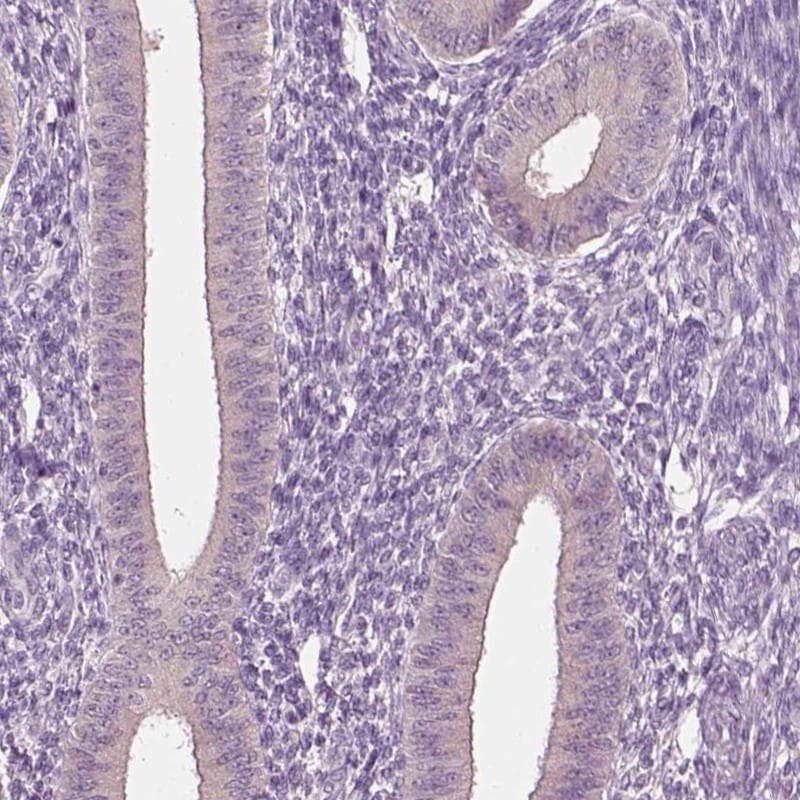

- Submitted by

- Invitrogen Antibodies (provider)

- Main image

- Experimental details

- Immunohistochemical staining of CLPSL1 in human endometrium using CLPSL1 Polyclonal Antibody (Product # PA5-67272) shows low expression as expected.